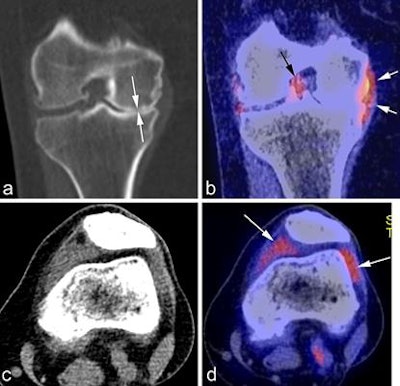

Using F-18 FDG PET can facilitate imaging of active metabolism and visualization of bone turnover changes, and PET can show active synovitis, which has been associated with knee pain in osteoarthritis patients, Hayashi noted. To overcome the major limitations of PET, particularly its relatively low anatomical resolution, use of PET/CT and PET/MR hybrid imaging has been explored, and the feasibility has been demonstrated for assessment of early metabolic or morphologic markers across multiple tissues.

A: Coronal CT reformatted image shows marked medial joint space narrowing reflecting advanced osteoarthritis (white arrows). B: Corresponding fused PET image shows glucose accumulation around the medial meniscus reflecting focal synovitis (white arrows). Another focus of synovitis is shown around the posterior cruciate ligament in the intercondylar notch (black arrow). C: Axial CT image in soft-tissue kernel shows distension of the joint capsule, but is not able to differentiate between fluid and synovitis. D: Matched axial PET image shows marked glucose uptake in the medial and lateral peripatellar regions reflecting hypermetabolic active synovitis (arrows). Image courtesy of Dr. Daichi Hayashi et al and BJR."SPECT/CT is another potential hybrid imaging that can be utilized, and it has been explored recently in the literature," Hayashi said. "But right now these hybrid imaging techniques are not routinely performed in a clinical setting, and available literature evidence is limited. And there are very few studies showing the feasibility of these techniques in osteoarthritis imaging research. For these techniques to be used in clinical practice, there is still a long way to go."